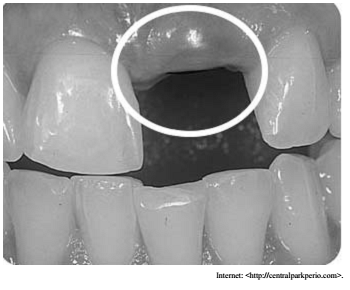

Na imagem precedente, a parte coronal e o parafuso de proteção do implante podem ser vistos por transparência através da gengiva. No que se refere ao controle dessa situação clínica, julgue o item seguinte.

Idealmente, a faixa da mucosa ceratinizada deveria ser de 3 mm ou maior e a espessura gengival de 2 mm em implantes em áreas estéticas; na ausência dessas características, enxertos são indicados.